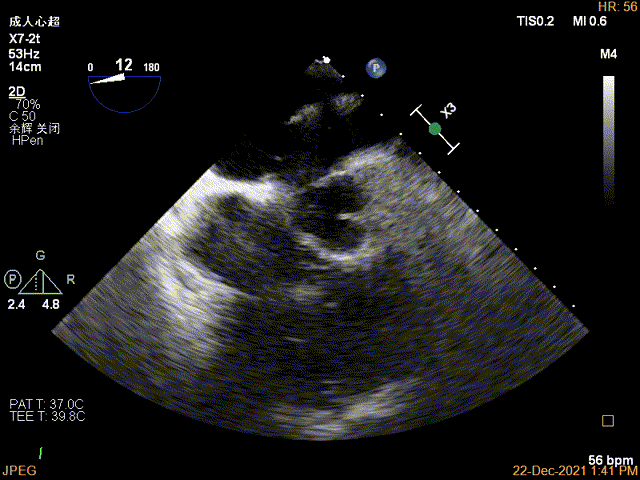

术前超声评估

术前超声诊断

Bicom:MR(重度),反流束宽22mm,反流面积24.2cm²,PISA法定量EROA:2.3cm²,Rvol:274ml,RF:57%,r:16mm。

二尖瓣反流频谱呈全收缩期

肺静脉血流频谱呈收缩期反向

3D MV View:P2区脱垂

3D-color MV view:大量反流,起源于2区

Qlab软件勾画估测瓣口面积约:7.19cm²

二尖瓣口平均跨瓣压差:4mmHg

TEE Bicom view:二尖瓣后叶P2区大范围脱垂,部分累及1区及3区

Color-view:极大量反流,主要来源于2区